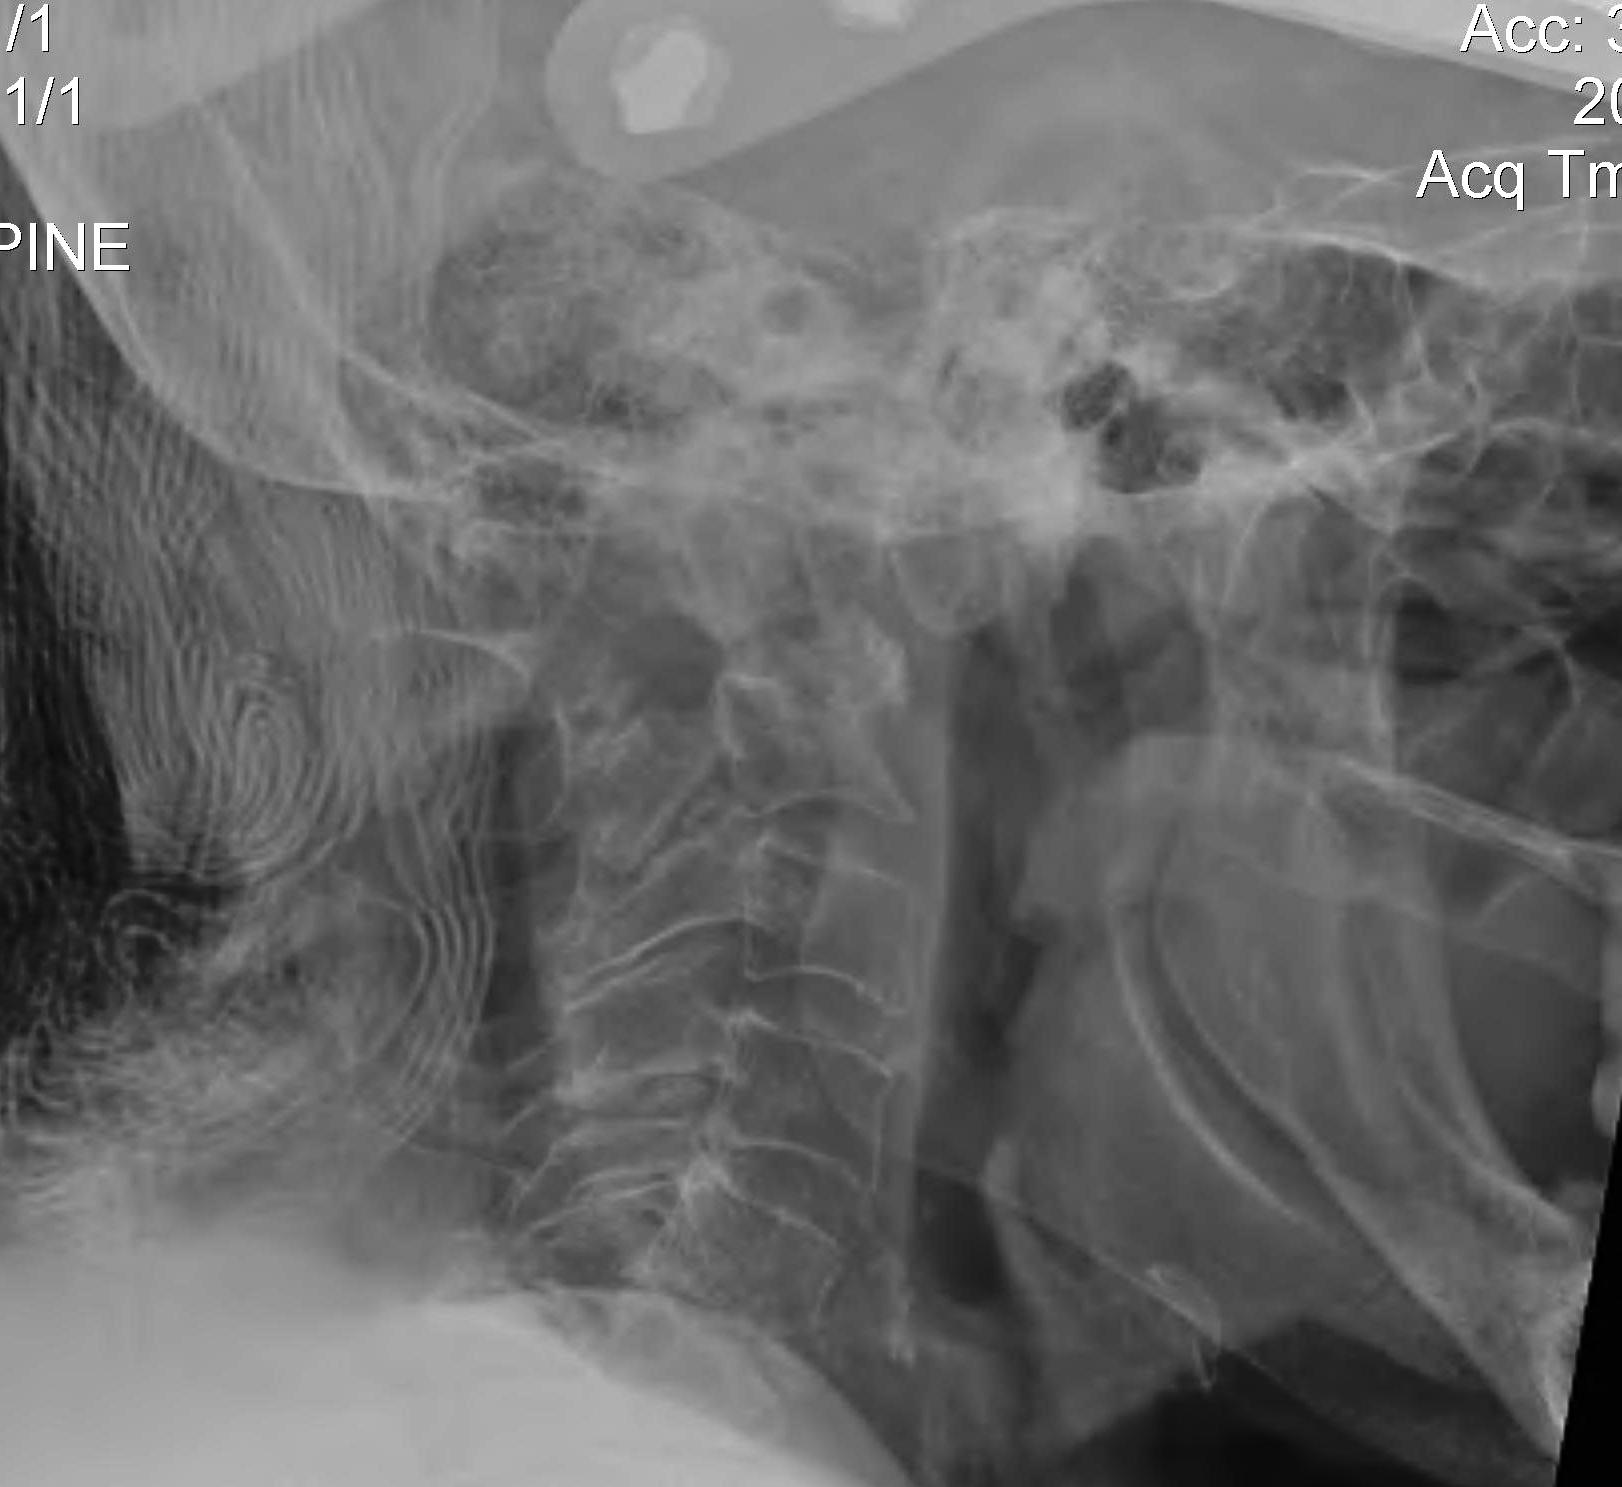

Subaxial Subluxation (SAS)

Definition

Anterior subluxation of one vertebral body on another

Results in spinal stenosis

Diagnosis

A. Instability on Flexion / Extension views

- > 3mm

- > 11o

Anterior subluxation of C3 on C4

B. Space available for cord / SAC

- subaxial canal diameter on lateral

- < 13 mm high incidence neurology

Pathology

Facet erosions / ligament incompetence

May see at multiple levels with stepladder type deformity & kyphosis

Can occur beneath previous cervical fusions including C1/C2